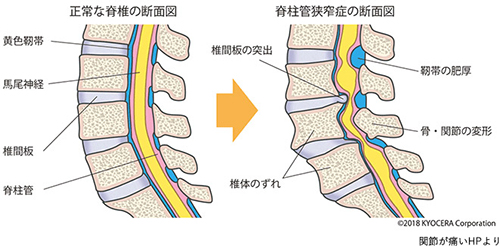

腰部脊柱管狭窄症

脊椎(腰の骨)が変形して、馬尾(神経)が圧迫されて起こる病気です。

原因は?

加齢が原因で、腰にある椎間板という軟骨や骨が変形し、脊柱管が狭くなり、馬尾神経や神経根が圧迫されて起きます。